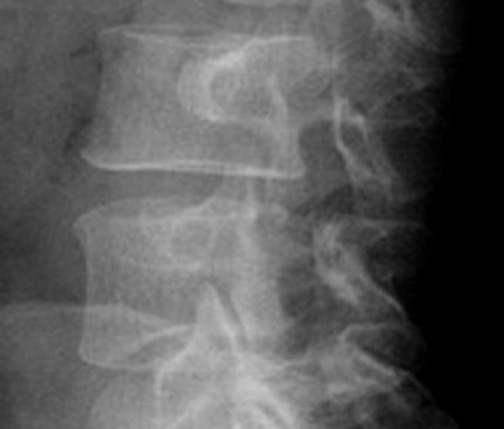

Identify parts of the Scotty dog. Click the image for labeling.